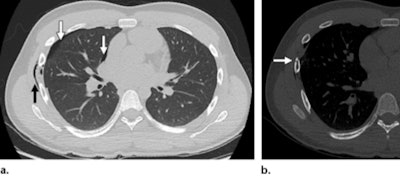

- Thoracic: Rib fractures, pneumothorax, pulmonary contusion, pneumomediastinum

- Abdominal: Pancreas, small bowel, mesentery, liver, spleen, adrenal gland (liver lacerations may present as linear hypoattenuating lesions; spleen lacerations range from linear to branching patterns)